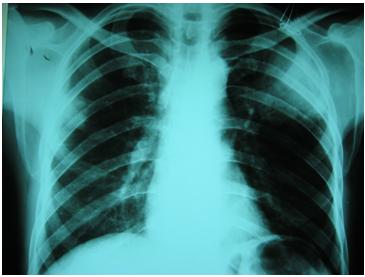

-Chụp x-quang phổi thay đổi hình ảnh khác nhau, gồm các hình thái như thâm nhiễm mịn, nốt rải rác, thâm nhiễm thùy phổi dính liền nhau tiến triển đến đông đặc và hóa khoang phổi;

-Kiểm tra x-quang phổi có thể cần thiết để tìm thấy các bệnh lý và loại khỏi bệnh cảnh viêm mủ phổi;